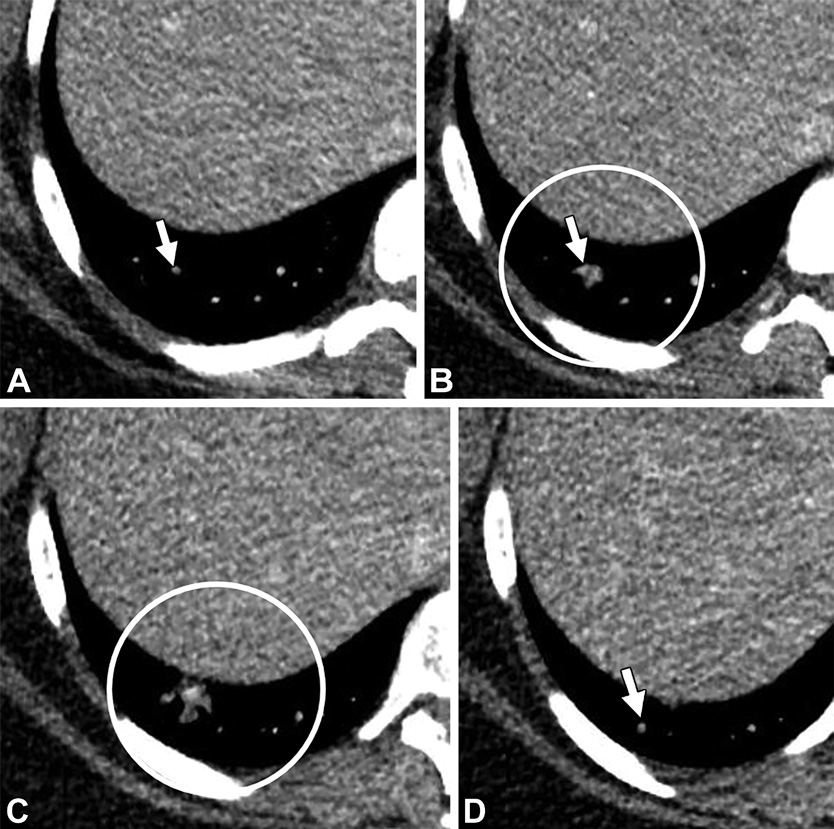

肉芽肿。31岁男性,有遗传性出血性毛细血管扩张症家族史。(A至C)轴位CT增强图,可见左肺下叶病变,伴供血动脉(白色箭头)以及中心高密度(白色星号),未见引流静脉。(D)随诊CT5年后,病变变小(白色星号),开始钙化。提示肉芽肿。